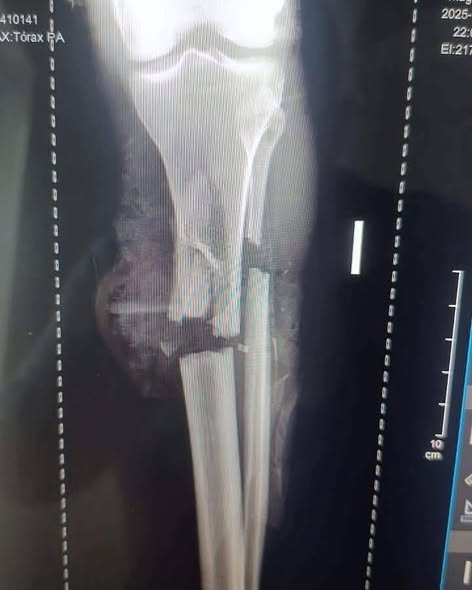

El hecho, que puso en peligro a seis personas, incluyendo cuatro menores de edad, dejó a Bautista Vásquez en estado crítico en la Clínica Unión Médica, tras sufrir amputación de la pierna izquierda y fractura de la derecha, convirtiéndose en uno de los casos más impactantes de violencia del año.